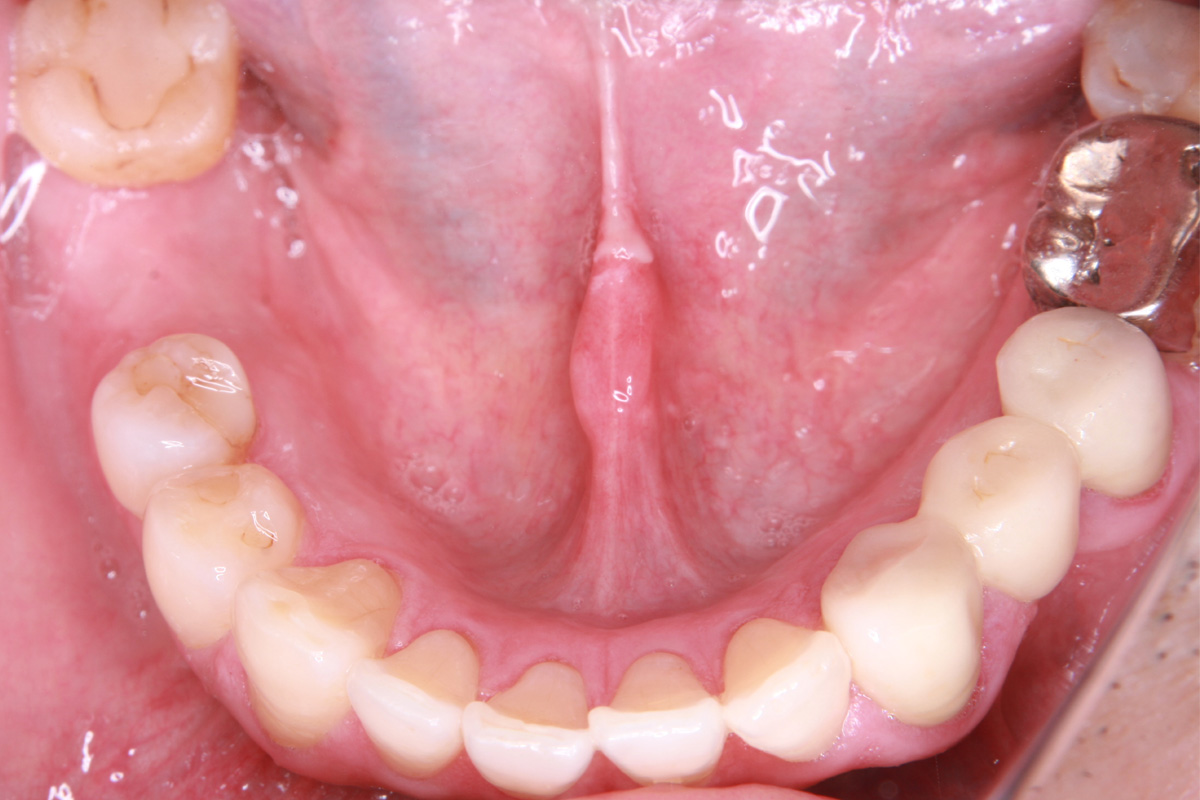

インプラント手術から3ヵ月後、型どりをして、仮歯を製作しました。

仮歯の調整期間を経て、セラミックの歯が入りました。

レントゲン画像 治療前 インプラント治療後